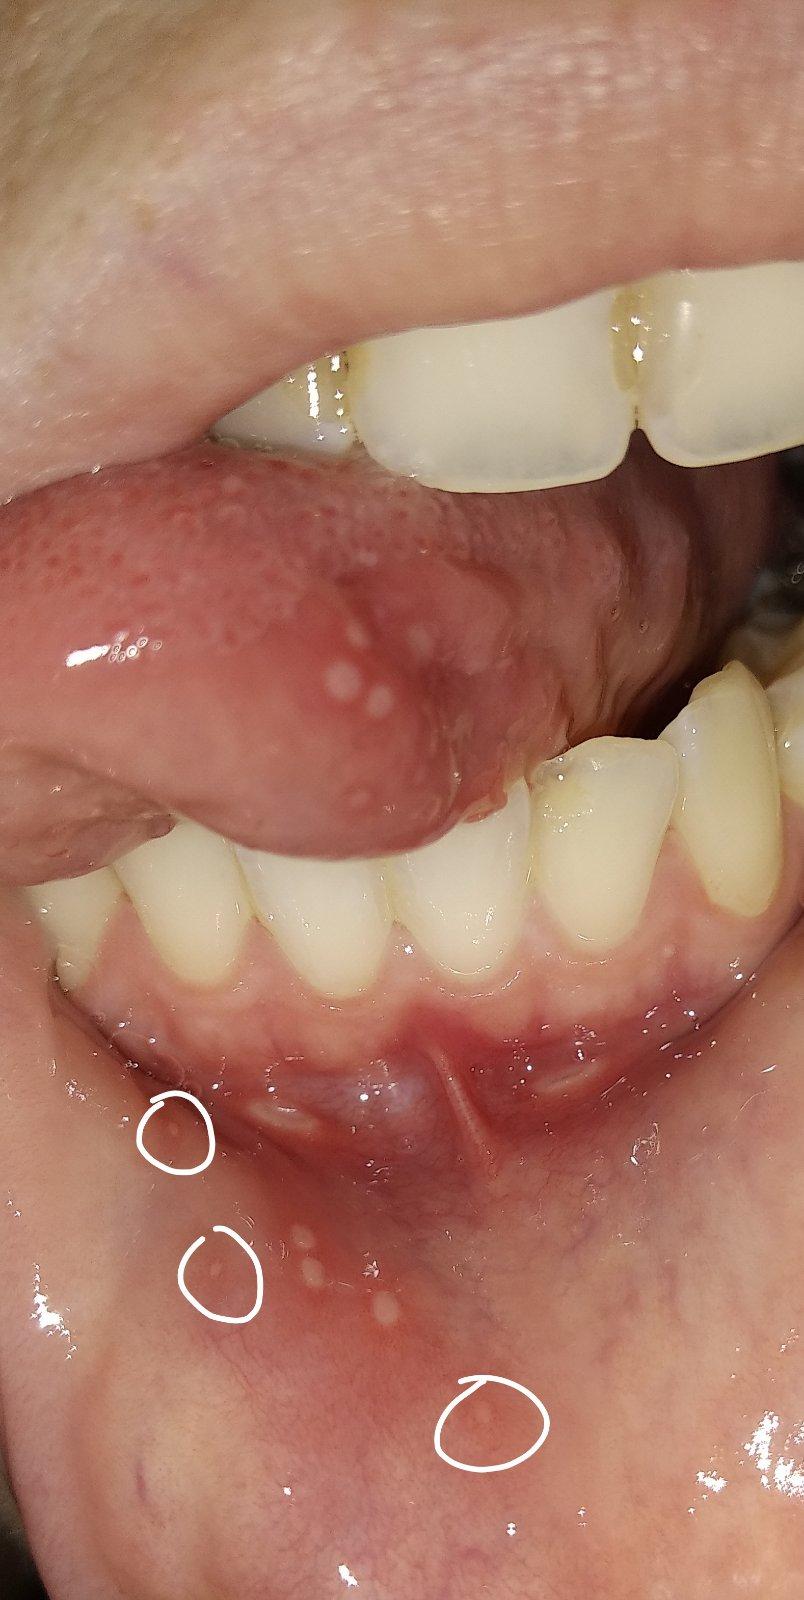

Baby, ktoré máte problém s častými aftami, čo vám zaberá?... skúšala som propolis, tea tree, taký gélik Lips, homeopatiu borax, ústnu vodu, pálenku, pastu meridol a nič nezaberá absolútne... najhoršie na tom je že drobec začal mať rovnaký problém a teraz ich máme každý 1-2 mesiace.. snažím sa aby nebol v kontakte s mojimi slinami ale poznáte to..neustrážim sa, dám mu napiť z môjho pohára, dám mu do úst moju lyžicu a tak... tentokrát nakazil on mňa, mal skôr a mne sa včera vyhodili, 4 na jazyku, 2 pri spodnej pere...aaach je to na nervy toto štípe to jak ďábel...tu bude asi nejaký vnútorný problém ale nerada by som to riešila cez lekárov a chémiu...drobec mi odmieta jesť, stále si pchá pršteky do pusy ale nie zo zúbkov, keď sú zúbky kuše si do nich, teraz len prikladá...ach viem ako sa musí cítiť ☹

A mne nezabera nic.a to ich mam 2_3krat za mesiac 😢 aj teraz mam uz par dni.chodim na doplnenie zelezia infúzie.beriem aj B12 inekcie,bekomplex forte,D,acidum folikum,inunologia dopadla bez nalezu,alergia sa nepotvrdila,no aj tak od januara sa to rapidne zhorsilo a vobec neviem z coho.uz som mala aj fest zapal dasien z toho.